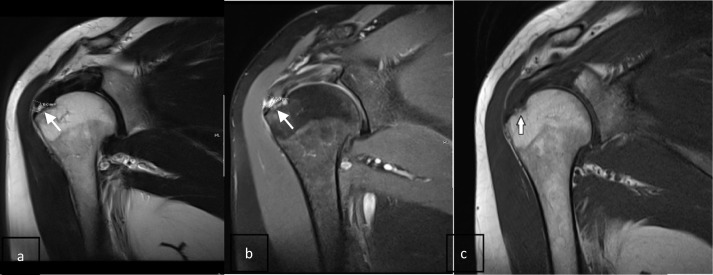

회전 근개(힘줄) 파열의 MRI

MRA (Magnetic Resonance Arthrography)입니다

그 방법은 어께 관절 부분에 염색약을 주사한 후, MRI 촬영을 하면

어께 회전 근개 파열이 있는 곳으로 염색약이 새어 나가서

어께 관절의 정확한 이상 부위를 쉽게 알 수 있도록 하는 것입니다

위의 그림에서 하얗게 보이는 부분이 염색약 입니다